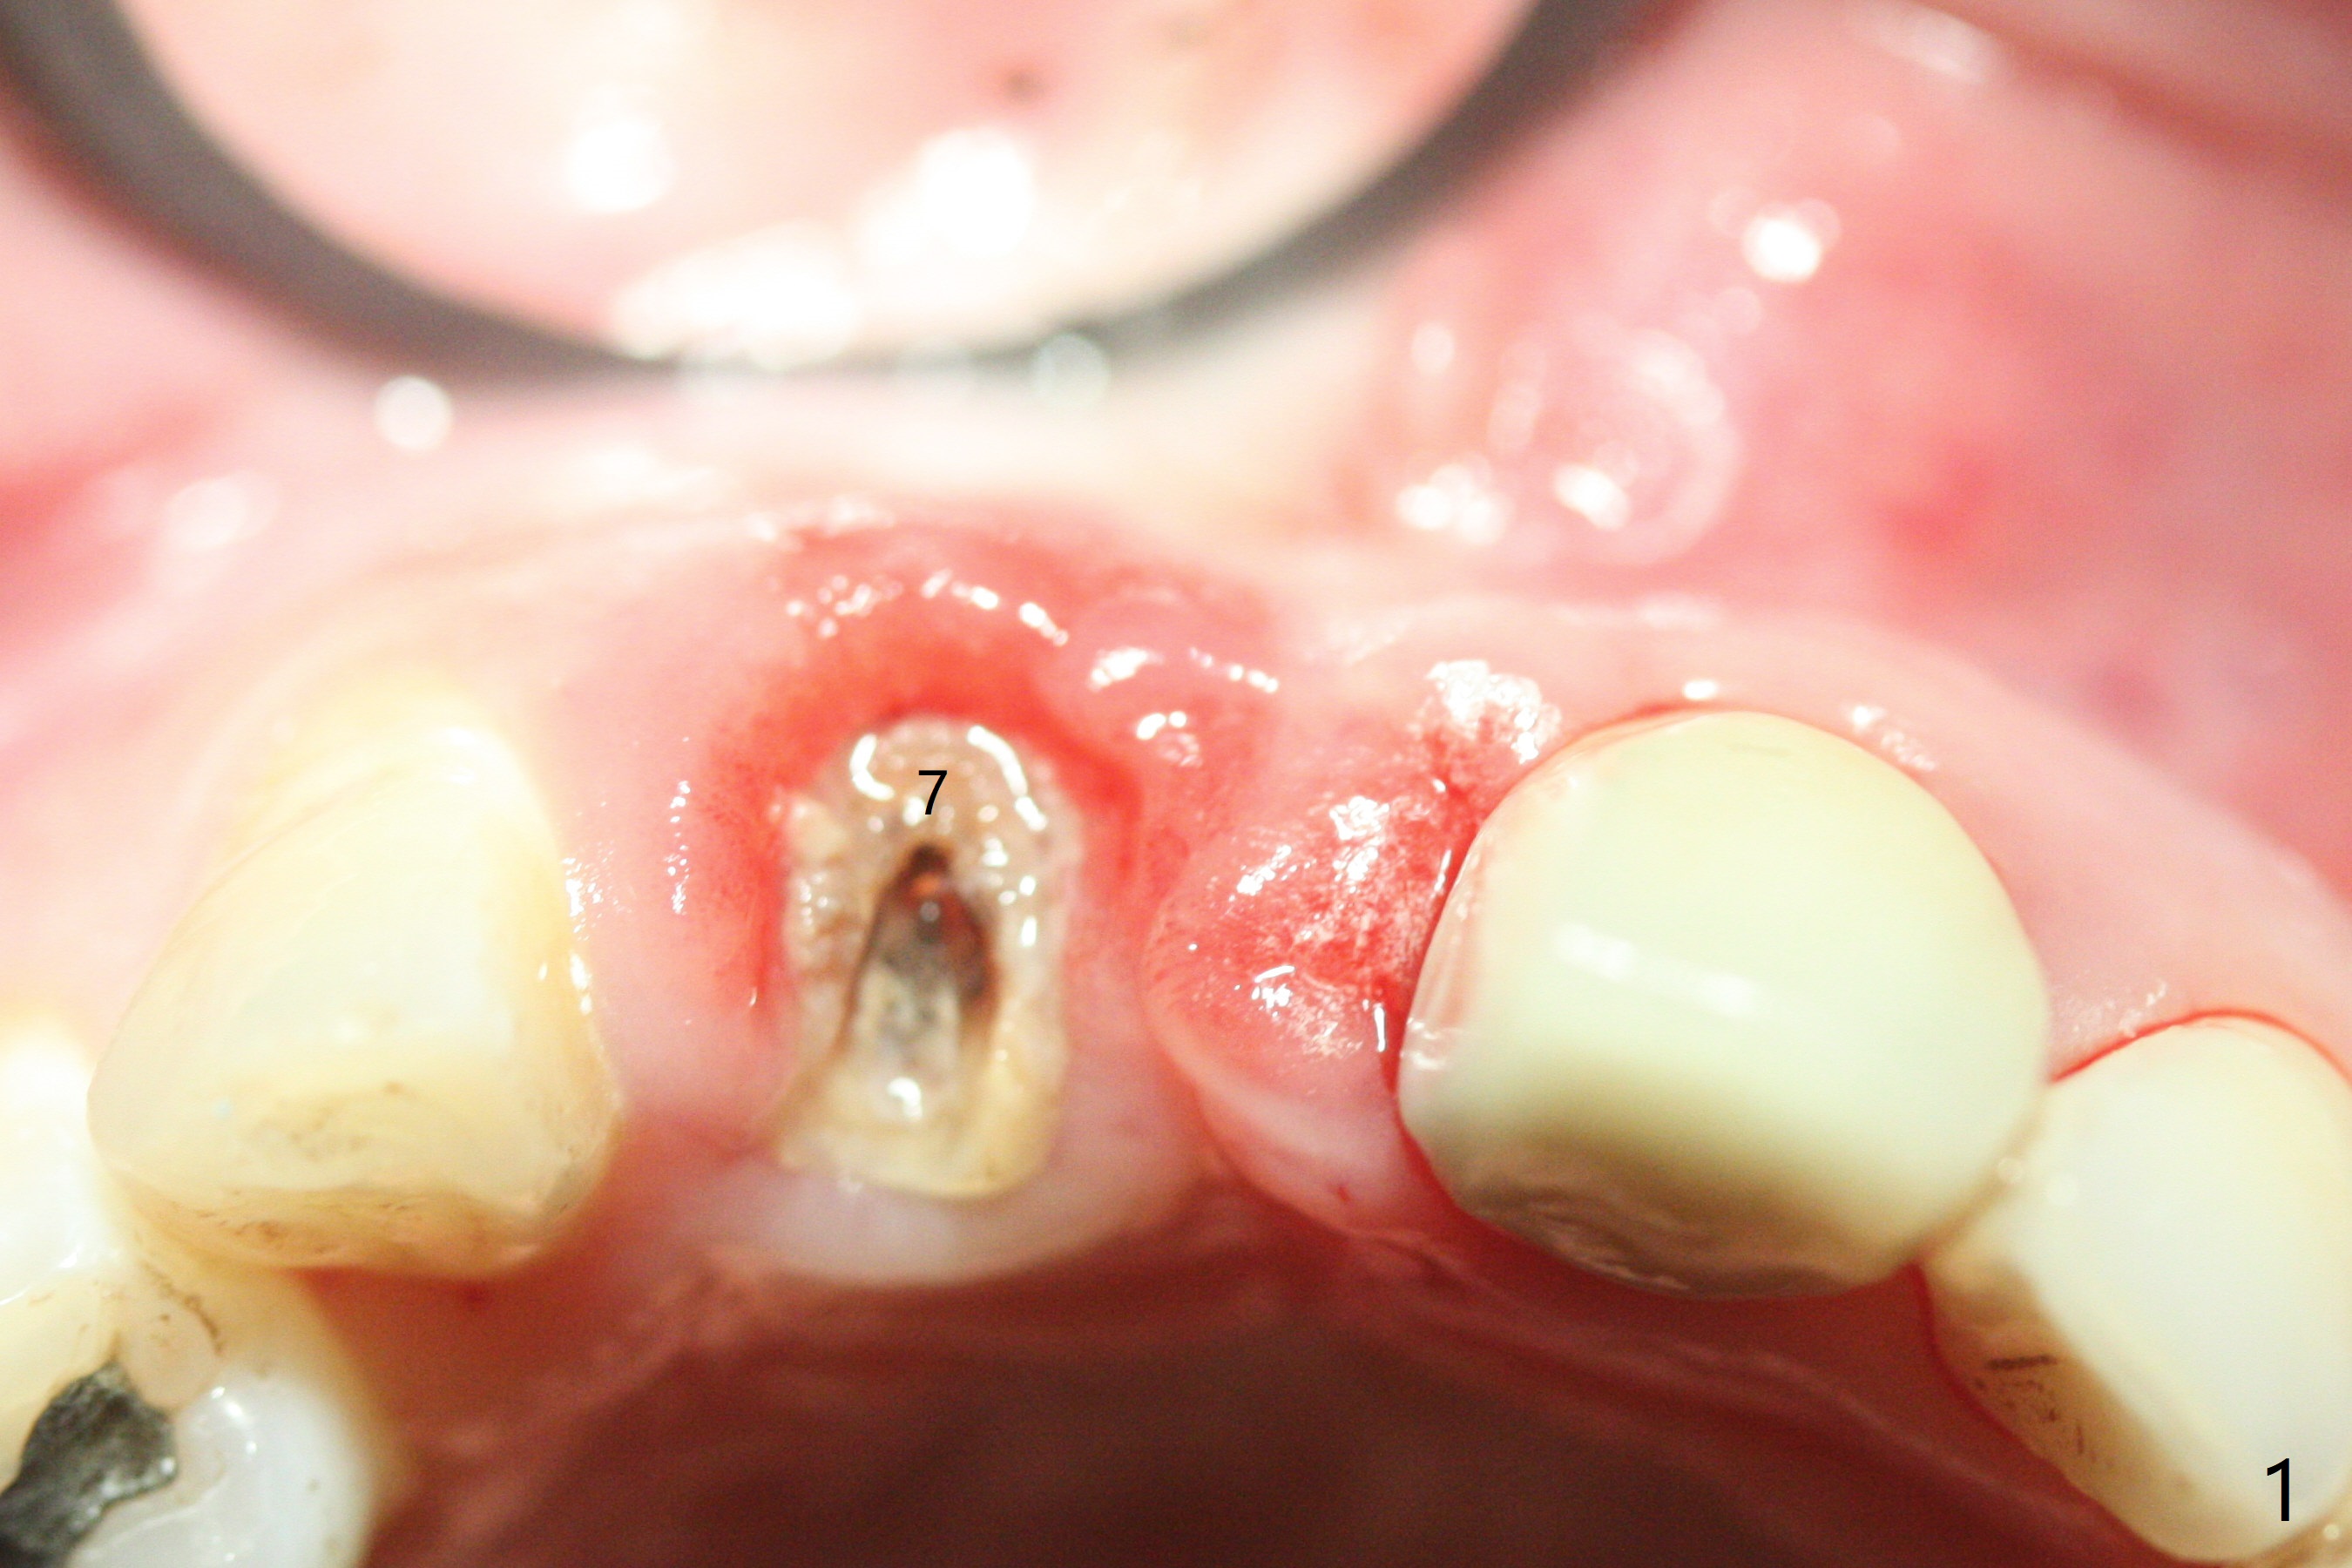

拆除部分桥发现:中,侧切牙牙龈红肿(图一),不利于切口和伤口愈合。不过还是在中切牙区切开,牙龈相当厚,有利于今后牙龈形成凹陷和乳头。坏消息是近远中距离太短,不利于植牙以及今后局部卫生维护,所以决定只在侧切牙种植(图二,三),完成钻洞后,颊侧根尖穿孔植骨,然后植入植体,即刻放置修复基台(图四 (*:牙龈乳头)),暴露基台牙龈缘,制作临时悬臂桥 (图五),两个中切牙牙冠长度差不多,插入临时桥时颊侧牙龈乳头基本形成(图六:*),缝合前颊侧,腭侧牙龈瓣下放置粘性骨块(图七,八:* )和PRF膜(图七:^)。最后使用牙周敷料。但愿术后牙龈炎症消失,形成良好牙龈乳头和pontic concavity。 其实由于口腔卫生习惯,术后十七天颊侧牙龈仍红肿(图九),而腭侧正常。如果口腔卫生改善而红肿依然存在,让实验室制作临时桥。术后一个月颊侧牙龈红肿好些(图十),好像骨粉丢失少许,可能与水枪使用有关。右上1牙冠显得太短(*)。也太肥大,因为右上1切缘太颊侧,与左上1对比(图十一:*)。由于颊侧牙龈(图十二:B)术中推向颊侧,与腭侧(P)牙龈之间放置大量粘性骨粉,术后一个月骨粉(<)形成牙龈,形成凹陷。颊侧萎缩不再明显了。右上1牙冠颈部多加些树脂,牙齿就显得长的多(图十三:箭头)。与侧切牙之间颈部故意留下间隙(*),让牙龈入位(空箭头),形成龈乳头。当右上1临时牙冠切缘(图十四:*)移到腭侧,外形改观不少。下次改善侧切牙唇侧。术后两个月三个星期牙龈红肿好像减轻,牙龈没有进入切牙间隙,干脆用树脂关闭(图十五:> <)。下次减少侧切牙切缘(^),适当增加中切牙长度(上提牙龈)。术后3.5个月植体好像整合,基台完全就位(图十六)。术后3.5个月Pontic凹陷形成,但是1,2之间龈乳头始终无法形成(图十七)。以后类似病例应该多种植一个。此例草率取模,可能需要临时粘固,观察植体近中颊侧所谓瘘道,必要刮治。由于比色不佳,需要实验室颜色更改,病人强化卫生,术后七个月,永久性牙冠粘固前,局部牙龈健康(图十八)。